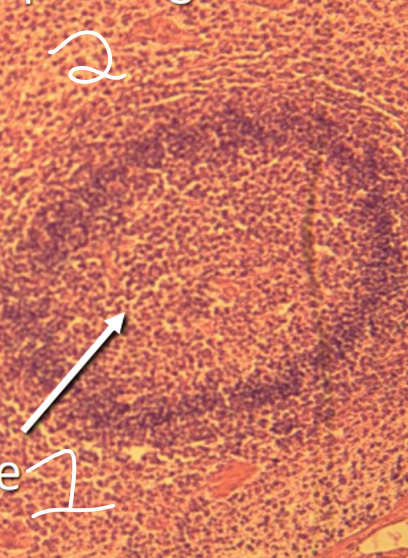

Rate

1- rate

2 -» ce qui est à l’extérieur

1- pulpe blanche 2- pulpe rouge